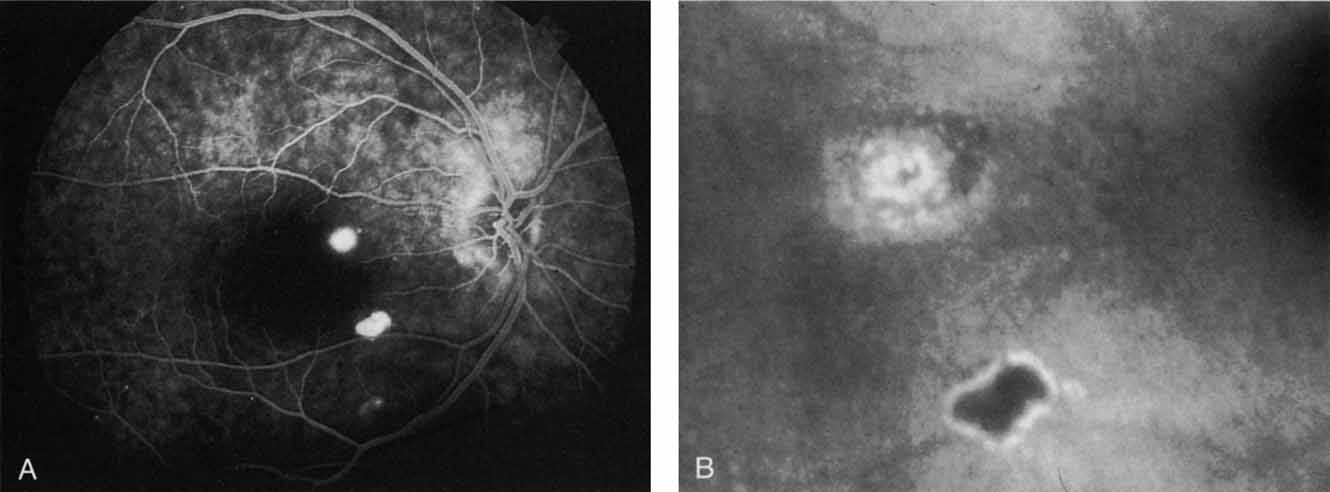

In multiple evanescent white dot syndrome (MEWDS), the typical fluorescein appearance in the acute phase of the disease involves early-phase hyperfluorescence of dots in a ring formation, corresponding to the clinically evident lesions.60 In general, these dots are found only in the posterior pole. Interestingly, ICG angiography reveals an increased number of lesions beyond those clinically evident. The angiogram initially reveals a stellate pattern of hypofluorescent spots in a ring formation.61 In the later phases of ICG angiography, however, there are more widely distributed areas of hypofluorescent spots, frequently extending far into the periphery (Fig. 15).

Fig. 15 A. Composite montage of the ICG angiogram in a patient with multiple evanescent white dot syndrome (MEWDS). Note the numerous large hypofluorescent spots with overlying smaller hypofluorescent dots. These lesions evident on the ICG study far outnumbered the clinically apparent ones. The arrow demonstrates the area that was enlarged in B. B. An interesting finding on the ICG corresponds to these areas of relative hyperfluorescence of the choroidal vessels, which indicate a localized inflammatory reaction.

The widespread nature of these lesions would help to explain the generalized nature of this condition, which is exemplified by abnormalities frequently detected in electroretinographic testing.62 In addition, some patients with MEWDS have been reported60,63 to have blind-spot enlargement on visual field testing. This was unexplained by either clinical or fluorescein angiographic examination and was attributed to an idiopathic peripapillary retinal dysfunction. ICG angiography in some of these patients has revealed confluent areas of hypofluorescent spots surrounding the optic nerve64 (Fig. 15A). This may provide the first evidence of a region of hypoperfusion or inflammation that may lead to secondary dysfunction and blind spot enlargement. It has been shown that resolution of the enlarged blind spot and return of vision does not correlate completely with the disappearance of hypofluorescent areas on ICG angiography; these lesions often remain visible on ICG study. These findings suggest that MEWDS may result in persistent abnormalities in choroidal circulation, even after vision has been restored.